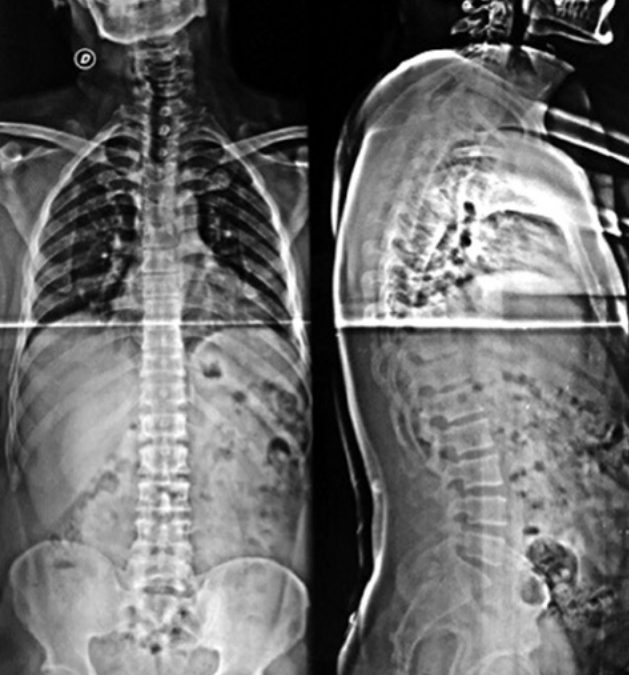

Cierre dural primario utilizando un nudo extracorpóreo